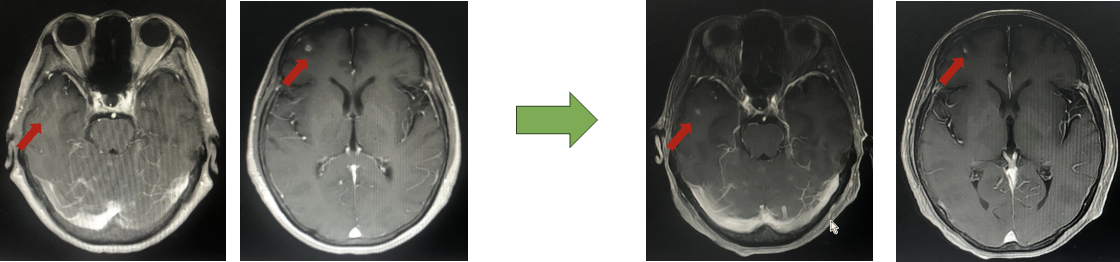

2022年10月头颅MR:脑内多发异常强化灶,结合病史考虑转移。(新发脑转移)

二线治疗方案:吡咯替尼 400mg/d + 卡培他滨 1.0g 2次/d 1/21d(依据PHENIX研究)

PHENIX研究:基线有脑转移患者,吡咯替尼方案可延长中位PFS近3月,有效抑制脑转移进展。

疗效评估:PR

2023年9月头颅增强MR:脑内多发异常强化灶,部分较前缩小。

二线PFS:19月

二线解救治疗(吡咯替尼联合卡培他滨):脑转移后采用吡咯替尼联合卡培他滨(PHENIX研究支持)符合《中国临床肿瘤学会(CSCO)乳腺癌诊疗指南》推荐。同时河南省肿瘤医院闫敏教授团队发起的一项吡咯替尼联合卡培他滨治疗HER2阳性脑转移的多中心、前瞻、单臂、开放的Ⅱ期PERMEATE研究,同样支持二线尽早选择吡咯替尼的联合治疗,无论患者是否曾接受过局部放疗,吡咯替尼联合卡培他滨的治疗方案均能为HER2阳性乳腺癌伴脑转移的患者带来显著的长期生存期获益,尤其在未接受放疗的患者中尤为显著。这同时也提示,乳腺癌新发脑转移不必急于局部治疗,某些具有中枢活性的抗肿瘤药物,或可作为优先考虑的治疗选择。